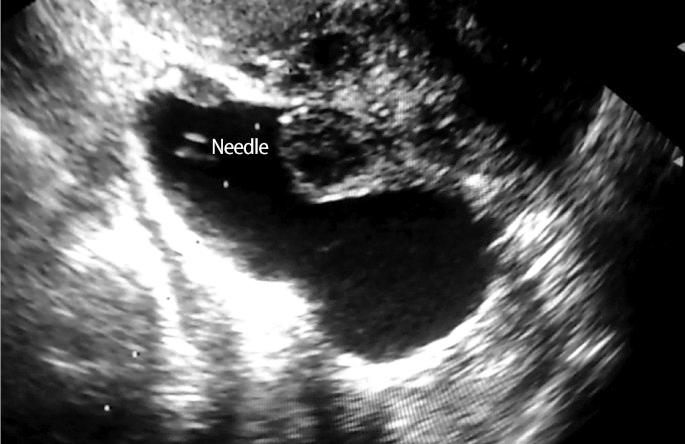

Many studies have demonstrated that hydrosalpinx has a detrimental effect on the outcome of IVF. Treating hydrosalpinges prior to the IVF procedure in women with hydrosalpinges is thought to improve the likelihood of successful IVF outcome. Vaginal ultrasound-guided aspiration of hydrosalpinx fluid (HSF) with injection of the sclerosing agent in situ might be simpler than invasive procedures like salpingectomy. Therefore, we carried out a retrospective study on the effects of ultrasound-guided HSF aspiration and injection of the sclerosing agent of ultrasonically diagnosed hydrosalpinx on IVF outcome.

许多研究表明,输卵管积水对体外受精(IVF)结局有不利影响。对于患有输卵管积水的女性,在IVF手术前治疗输卵管积水被认为可提高IVF成功的可能性。阴道超声引导下抽吸输卵管积水液(HSF)并原位注射硬化剂可能比输卵管切除术等侵入性手术更简单。因此,我们对超声引导下HSF抽吸及注射硬化剂治疗超声诊断的输卵管积水对IVF结局的影响进行了一项回顾性研究。